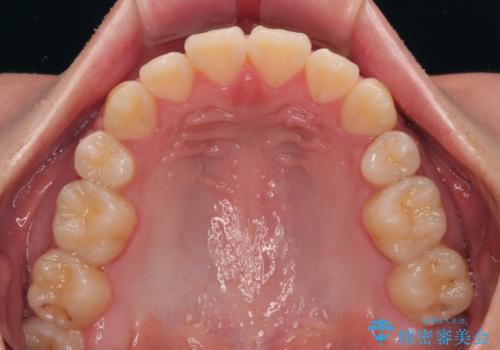

- クリアブラケット

- 1年6ヶ月

特に前歯のデコボコが顕著であり、上下左右第一小臼歯の4本を抜歯し、ワイヤー装置を使用して咬み合わせ高さを改善しながら、歯列を整えて行くこととしました。

移動が順調に進み、1年半の短期間で治療を終えることができました。

前方に突出した上顎前歯の傾斜も改善されました。